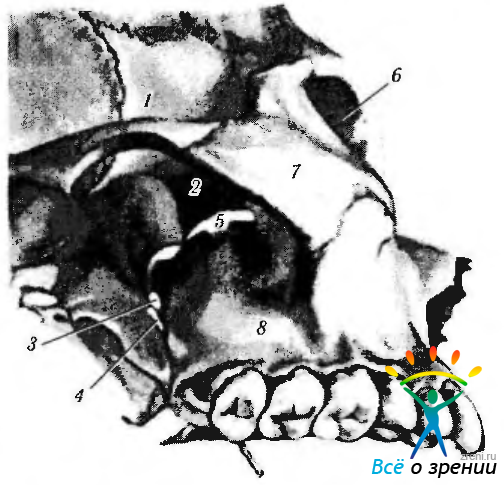

Анатомические особенности: фотографии ямок черепа, височной и подвисочной крылонебной